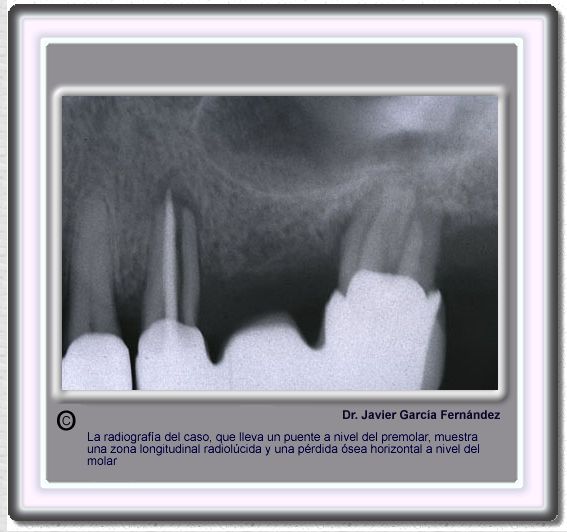

image377